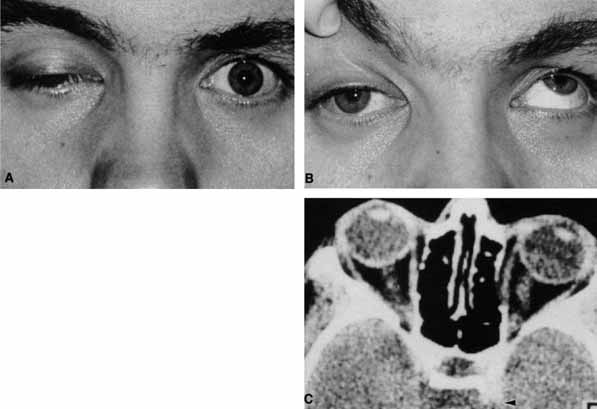

CASE 1 A 70-year-old woman presented with a 6-month history of progressive diplopia and ptosis. She demonstrated complete right third, fourth, and sixth cranial nerve palsies, and hypesthesia of cranial nerve V1 (Fig. 22A). The right pupil was dilated. Computed tomography (CT) disclosed an intracavernous aneurysm (see Fig. 22B). The so-called superior orbital fissure syndrome occurs when an infiltrative, inflammatory, or ischemic event occurs within the superior orbital fissure, but not in the orbital apex.4 A complete superior orbital fissure syndrome occurs when all the neurovascular components passing through the superior orbital fissure are damaged, producing a total ophthalmoplegia, ptosis, and anesthesia of cranial nerve V1 (see Fig. 22A). The pupil may be dilated, miotic, or midposition and fixed, depending on the balance of parasympathetic and sympathetic damage. The superior ophthalmic vein, best seen on CT, may be dilated if venous outflow from the orbit is obstructed. Clues to venous outflow obstruction are increased intraocular pressure, fullness of the upper eyelid, and hyperemia of the deep Tenon's vessels. Ophthalmoscopically, the retinal veins may be dilated. The effect of a lesion in the superior orbital fissure or the anterior cavernous sinus cannot be differentiated clinically (see Fig. 22B). When the posterior cavernous sinus becomes involved, hypesthesia of cranial nerve V2 may also be present. The only difference between a superior orbital fissure syndrome and an orbital apex syndrome is the presence of visual loss caused by optic nerve involvement. Visual acuity, color vision, or the visual field are abnormal. An ipsilateral relative afferent pupil defect is present. CASE 2 A 30-year-old man noted diplopia and right ptosis for the past month. The patient demonstrated normal vision and symmetric pupils but had a neurogenic ptosis (Fig. 23A) and limited right supraduction (Fig. 23B). Otherwise his extraocular movements were full. CT demonstrated an intracranial aneurysm of the posterior communicating artery aneurysm (Fig. 23C). Anatomically, the third cranial nerve branches into its superior and inferior divisions as it enters the orbit through the superior orbital fissure. Superior branch damage results in ptosis (levator muscle) and decreased supraduction (superior rectus muscle). Inferior branch damage results in decreased adduction (medial rectus), decreased infraduction (inferior rectus), decreased excycloduction (inferior oblique), and a dilated pupil (parasympathetic). Anatomically, a cranial nerve III branch nerve lesion seems to imply an anterior cavernous sinus or orbital apex localization. However, functionally, the third cranial nerve may bifurcate in the intracranial portion of the nerve, so cranial nerve III branch nerve palsies have been demonstrated with intracranial lesions. The localizing finding of a cranial nerve III branch nerve lesion is therefore not absolute (see Fig. 23).46 CASE 3 A 12-year-old child was referred by his school nurse because he had been complaining intermittently of double vision and the nurse had noted intermittent right ptosis. The child presented with a right ptosis and limited infraduction of the left eye (Fig. 24A). The ptosis worsened with prolonged up-gaze. A Cogan lid twitch was noted on the right with upward saccades. Injection of 1 mg of edrophonium resulted in complete resolution of diplopia and ptosis (Fig. 24B). The diagnosis was myasthenia gravis. Most orbital and cavernous sinus lesions produce afferent and efferent palsies in an anatomic pattern, for example, the superior orbital fissure has cranial nerves III, IV, VI and V1. When the pareses are not localized anatomically, or when there is variability in findings over time, one should include carcinomatosis or myasthenia gravis (see Fig. 24) in the differential diagnosis. Fatigability and a Cogan lid twitch strongly suggest myasthenia gravis. CASE 4 A 52-year-old woman presented with diplopia when looking to her right. She had noted a red right eye for the past 3 months (Fig. 25A). Visual acuity was 20/20 in both eyes and the pupils were normal. The right eye was limited in abduction. Forced duction testing showed abduction of the right eye to be restricted. Intraocular pressures were 23 mm Hg OD, and 15 mm HG OS. CT showed a dilated right superior ophthalmic vein (Fig. 25B) which was shown to be caused by a dural cavernous fistula. The right medial rectus muscle was also enlarged (Fig. 25C) because of blood engorgement, reducing muscle compliance, which accounted for the restricted abduction. Carotid cavernous fistulas can develop either as a result of trauma or spontaneously.47 A direct carotid cavernous fistula results from a tear in the intracavernous carotid artery with arteriolization of the cavernous sinus and superior orbital vein. Concomitant cranial nerve III, IV, VI, V1 and V2 paresis, elevated intraocular pressure, proptosis, and distention of the deep Tenon's vessels anteriorly (see Fig. 25A) with neuroradiologic evidence of an enlarged superior ophthalmic vein are common (see Fig. 25B). Ophthalmoplegia may also occur on a restrictive basis because of engorgement of the extraocular muscles with blood (see Fig. 25C).36 Dural carotid cavernous fistulas occur where small branches of the intracavernous carotid rupture, allowing access of arterial blood to the cavernous sinus. Typically, the findings are similar to a direct carotid cavernous fistula but of less magnitude. There is no history of trauma, and typically occurs in older persons. However, there is crossover between these two types of carotid cavernous fistula. An excessive ocular pulse tonographically may be helpful in the diagnosis of a carotid cavernous fistula in such cases.48 CASE 5 A 51-year-old woman was referred by her internist for left proptosis. The patient had noted diplopia for the past month but denied blurred vision or pain. Past history was significant for breast carcinoma requiring mastectomy. Vision was 20/20 in both eyes and the pupils were normal. Extraocular movements of the right eye were limited. Forced ductions were restricted. Exophthalmometry readings were 14 mm OD and 18 mm OS (Fig. 26A). CT disclosed a mass encircling the right globe (Fig. 26B). Biopsy disclosed metastatic scirrhous breast carcinoma retracting the right globe.